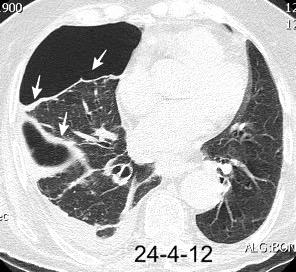

VIH+. 1 mes antes derrame pleural en el curso de una

infección